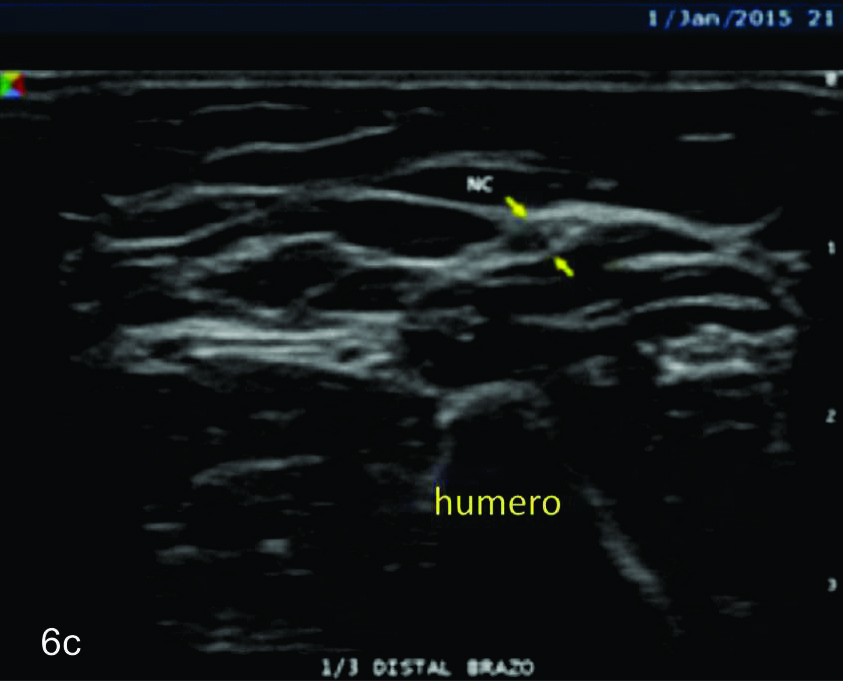

Figura 6

Nervio cubital

B- tercio medio del brazo,

C- tercio distal del brazo,

Figura 7

Serie de cortes axiales del nervio cubital desde su origen a nivel del hueco axilar hasta su terminación a nivel del canal de Guyon. Se identifica el mismo señalado por flechas amarillas y con las letras NC. AH-arteria humeral, PC- músculo prondador cuadrado, P- hueso pisciforme, Línea roja- ligamento anular del carpo, Línea amarilla- túnel de Guyon, Flecha azul- Arteria cubital-. A-tercio distal antebrazo, B- canal de Guyon.

Figura 14 c y d

Lesión traumática del plexo braquial luego de accidente en moto.

C y D- cortes comparativos longitudinales sobre el tronco medio del plexo braquial (C- izquierdo sano y D- derecho patológico), se demuestra la asimetría de la raíz media del plexo, la cual se demuestra en un corte longitudinal comparativo (señalada entre calipers amarillos). La flecha blanca en D señala un fragmento óseo desplazado debido a una fractura del proceso transverso vertebral que generaba conflicto con la raíz.